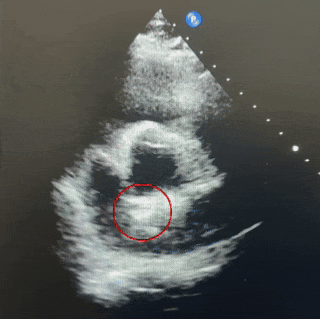

封堵器锁定成型后,超声下多切面确认封堵器盘面贴合,稳定夹持缺损。

主动脉短轴切面

四腔心切面

超声下可见封堵器稳定夹持在房间隔两侧,呈“Y”字形牢牢抱住主动脉,盘面贴合,形态良好。

在应对此类主动脉侧无残端且合并软缘的房间隔缺损时,若封堵器型号过小,可能无法获得稳定锚定,易发生封堵不全或移位风险;而选择偏大的封堵器虽能增加接触面积与摩擦力,但传统金属封堵器存在磨损主动脉、影响瓣膜功能甚至引起主动脉壁穿孔等风险。相较之下,MemoSorb可降解房间隔缺损封堵器凭借其专利降落伞成型锁定设计,相比金属封堵器有效提高1.8倍封堵器夹持力,即使面对缺损较大、边缘不良的情况,锁定后也可牢固夹持缺损。其采用的生物高分子材料,生物相容性更好,不易磨损主动脉根部。术后超声多切面显示封堵器形态良好,短轴切面下封堵器呈“Y”字形抱主动脉,盘面贴壁紧密,未见残余分流,术后患者自述头痛症状显著缓解。